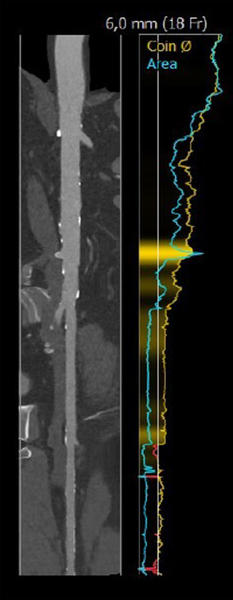

Case planning: CT

LAO 3° - cranial 19°

RAO 14° - caudal 9°